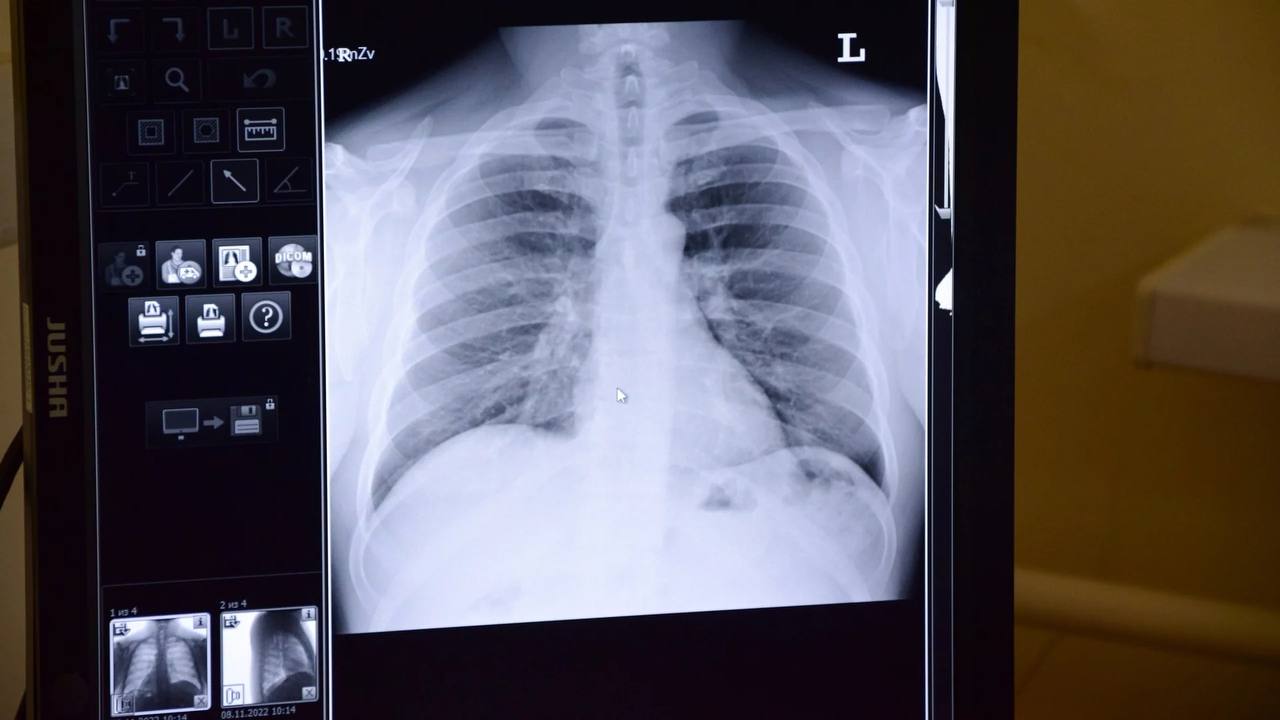

Микоплазменная пневмония — это инфекция, вызванная микоплазмами, которая ведет себя как вирус. На первый взгляд, она может напоминать обычную простуду, однако на самом деле поражает легкие, что приводит к развитию пневмонии, о которой человек может даже не догадываться.

Если вы заболели и не наблюдаете улучшения в течение 10–14 дней, это повод обратиться к врачу для проверки состояния легких. Обычная простуда не должна вызывать таких затяжных симптомов, и важно не упустить момент, когда лечение может быть наиболее эффективным.